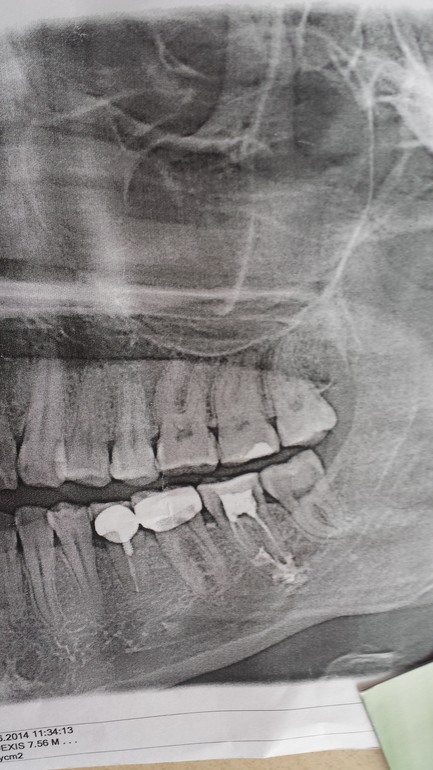

выход пломбировочного материала за верхушку корня

назад 6й зуб, каналы. Прикладываю снимок, на к-м виден выход

пломбировочного материала (со слов врача, эндометазон). После пломбирования не